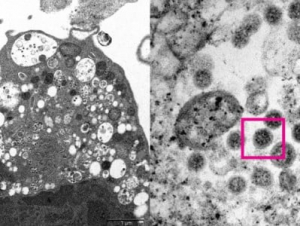

Գիտնականները ցույց են տվել, թե ինչպիսի տեսք ունի oմիկրոն...

Էլեկտրոնային մանրադիտակի միջոցով գիտնականները ստացել են SARS-CoV-2-ի նոր օմիկրոն շտամի պատկերը: Հոնկոնգի համալսարանի կայքում տեղադրված է երկու լուսանկար:...